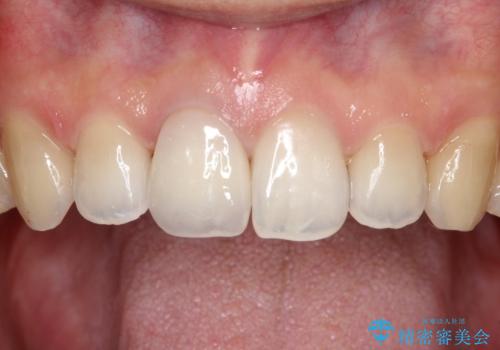

【前歯の被せ物】オールセラミッククラウン(エクセレント)

- 空隙歯列と前歯の変色を主訴に来院されました。

空隙歯列を矯正にて改善した後に歯冠修復を行なっております。

上顎前歯は根管治療後にオールセラミッククラウン(エクセレント)で修復を行なっております。

オールセラミッククラウン(エクセレント)では技工士さんの立ち会いのもと、より審美的な修復が可能です。